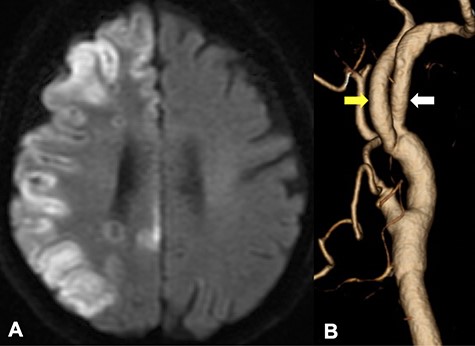

An 87-year-old female presented left homonymous hemianopsia and hemiparesis. She had a past medical history of hypertension and dyslipidemia. Diffusion-weighted imaging (DWI) in magnetic resonance imaging (MRI) showed infarction suggestive of high signal intensity lesions at the border zones between the anterior and middle and the middle and posterior cerebral artery territories (Fig. 1A). It also showed multiple infarctions in the territory of the posterior circulation. Computed tomography angiography (CTA) revealed severe stenosis, which nearly occluded the ICA bifurcation just proximal to the right ICA–PPHA bifurcation. The ipsilateral vertebral artery was absent, and the contralateral VA was rudimentary (Fig. 1B). PPHA originated from the posterior wall of the ICA at the C1–C2 intervertebral space and passed the hypoglossal canal (Fig. 1C). The basilar artery was supplied only by PPHA, and the anterior communicating artery and posterior communicating arteries were absent. CEA was planned to prevent further cerebral infarctions.

DWI on MRI showed infarction suggestive of high signal intensity lesions at the border zones between the anterior and middle and the middle and posterior cerebral artery territories (A); CTA from a posterior view revealed that PPHA (white arrow) originated from the posterior wall of the ICA (yellow arrow); the ipsilateral vertebral artery was absent, and the contralateral VA was rudimentary (B, gray arrow); CTA from a medial view revealed that PPHA entered the cranium through the hypoglossal canal (C, white line arrow).